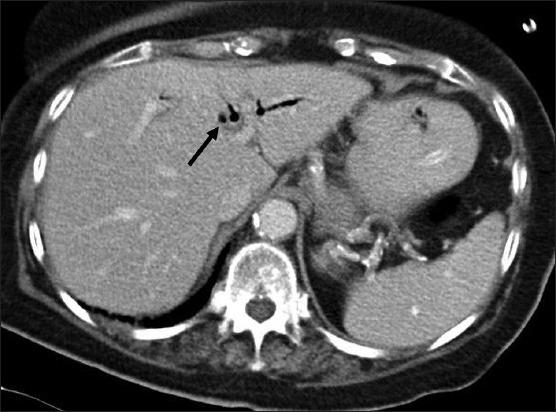

Gallstones ileus is an uncommon cause but important cause of small bowel obstruction. The gallstone enters the intestinal lumen via a fistula located in the duodenum (cholecystoduodenal), or rarely, in the colon (cholecystocolonic) or stomach (cholecystogastric). This may result in large bowel or gastric outlet obstruction (Bouveret's Syndrome). Gallstone ileus affects the elderly females pre-dominantly and is associated with a high morbidity and mortality rate if diagnosis and urgent surgical intervention are delayed. In this paper, we report on the case of an elderly lady who presented with classical symptoms and signs of small bowel obstruction. She was subsequently diagnosed with gallstone ileus due to a large gallstones lodged in the intestinal lumen. We perform a literature review on this rare disease and discuss the two main surgical approaches in managing this condition. Gallstone ileus should be considered in the differential diagnosis of small bowel obstruction especially in elderly women who have no history of abdominal surgery or abdominal hernia. Early intervention is important because of the high mortality rate due to the poor general condition that often exists in this subgroup of patients. There is no general consensus on gold standard surgical approach in these cases but a two-stage procedure (either enterotomy alone or enterotomy and subsequent cholecystectomy) has been shown to be associated with lower mortality rates.

胆石性肠梗阻是小肠梗阻的一种罕见但重要的病因。胆结石通过位于十二指肠的瘘管(胆囊十二指肠瘘)进入肠腔,或极少情况下通过位于结肠的瘘管(胆囊结肠瘘)或胃的瘘管(胆囊胃瘘)进入。这可能导致大肠或胃出口梗阻(布维耶综合征)。胆石性肠梗阻主要影响老年女性,如果诊断和紧急手术干预延迟,其发病率和死亡率较高。在本文中,我们报告了一例出现小肠梗阻典型症状和体征的老年女性病例。她随后被诊断为胆石性肠梗阻,原因是一枚大的胆结石嵌顿在肠腔内。我们对这种罕见疾病进行了文献综述,并讨论了治疗这种疾病的两种主要手术方法。在小肠梗阻的鉴别诊断中应考虑胆石性肠梗阻,尤其是在没有腹部手术或腹外疝病史的老年女性中。由于这类患者通常身体状况较差,死亡率较高,因此早期干预很重要。对于这些病例的金标准手术方法尚无普遍共识,但两阶段手术(单独肠切开术或肠切开术及随后的胆囊切除术)已被证明与较低的死亡率相关。